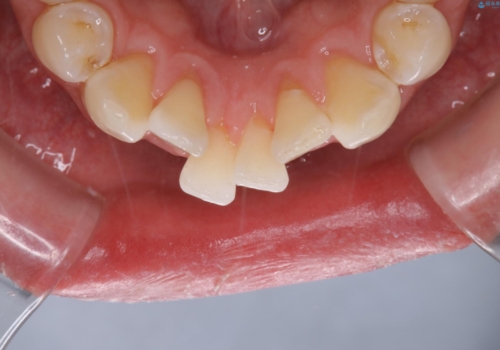

PMTCを初めてやったとのことで、全体的にステイン、プラーク、歯石が多く付着していました。これから虫歯の治療や矯正がスタートするため、歯茎が腫れていたり、汚れが付着していると、虫歯や歯周病が進行してしまうため、治療と並行してブラッシング指導、クリーニングを行っています。何よりも日々のクリーニング(ホームケア)が大切なため、頑張っています。

定期的なクリーニングを行っていても、毎日しっかりと磨けていなければ虫歯も進行しますし、まずはブラッシングの仕方、デンタルフロスと徐々にステップアップしていきます。